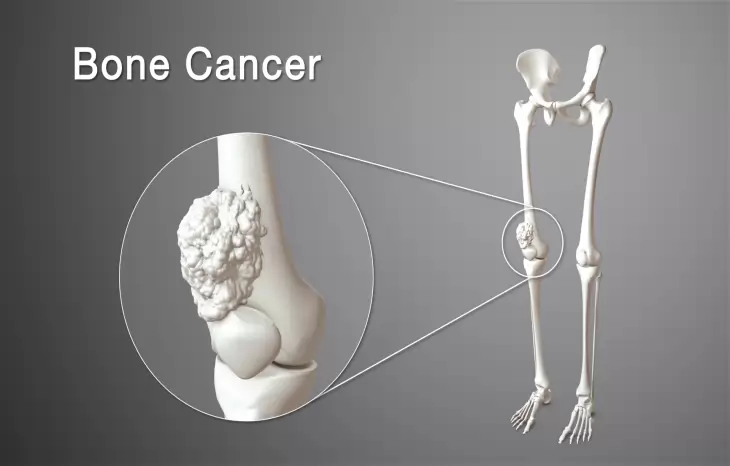

این نوع از سرطان استخوان در یاخته های غضروفی شکل می گیرد و دومین سرطان شایع استخوان است.

روش های عکس برداری می توانند به تعیین محل و اندازه ی تومورهای استخوان و گسترش یا عدم گسترش آن ها به سایر نقاط بدن کمک کنند. در این مقاله با علائم سرطان مغز استخوان و نیز روش های درمان آن آشنا می شوید. یک تومور رشد غیر طبیعی بافت در بدن است. سلول های توموری توانایی تنظیم کردن ندارند بنابراین سلول های بیشتری تولید می کنند و منجر به تشکیل یک توده می شوند در حالی که بسیاری از تومورها سرطانی.

این سرطان در سنین زیر 20 سالگی رخ می دهد و احتمال ابتلاء به آن با افزایش سن کم می شود. درمان سرطان استخوان انتخاب روش درمان بستگی به نوع اندازه مرحله سرطان سن و سلامت عمومی بیمار دارد. سرطان استخوان چیست انواع سرطان استخوان. چشم انداز بهبود سرطان استخوانی بستگی به عواملی مانند سن نوع سرطان استخوان گستردگی سرطان مرحله و احتمال گسترش بیشتر آن درجه دارد به طور کلی در مورد سرطان استخوان بسیار ساده تر است که.